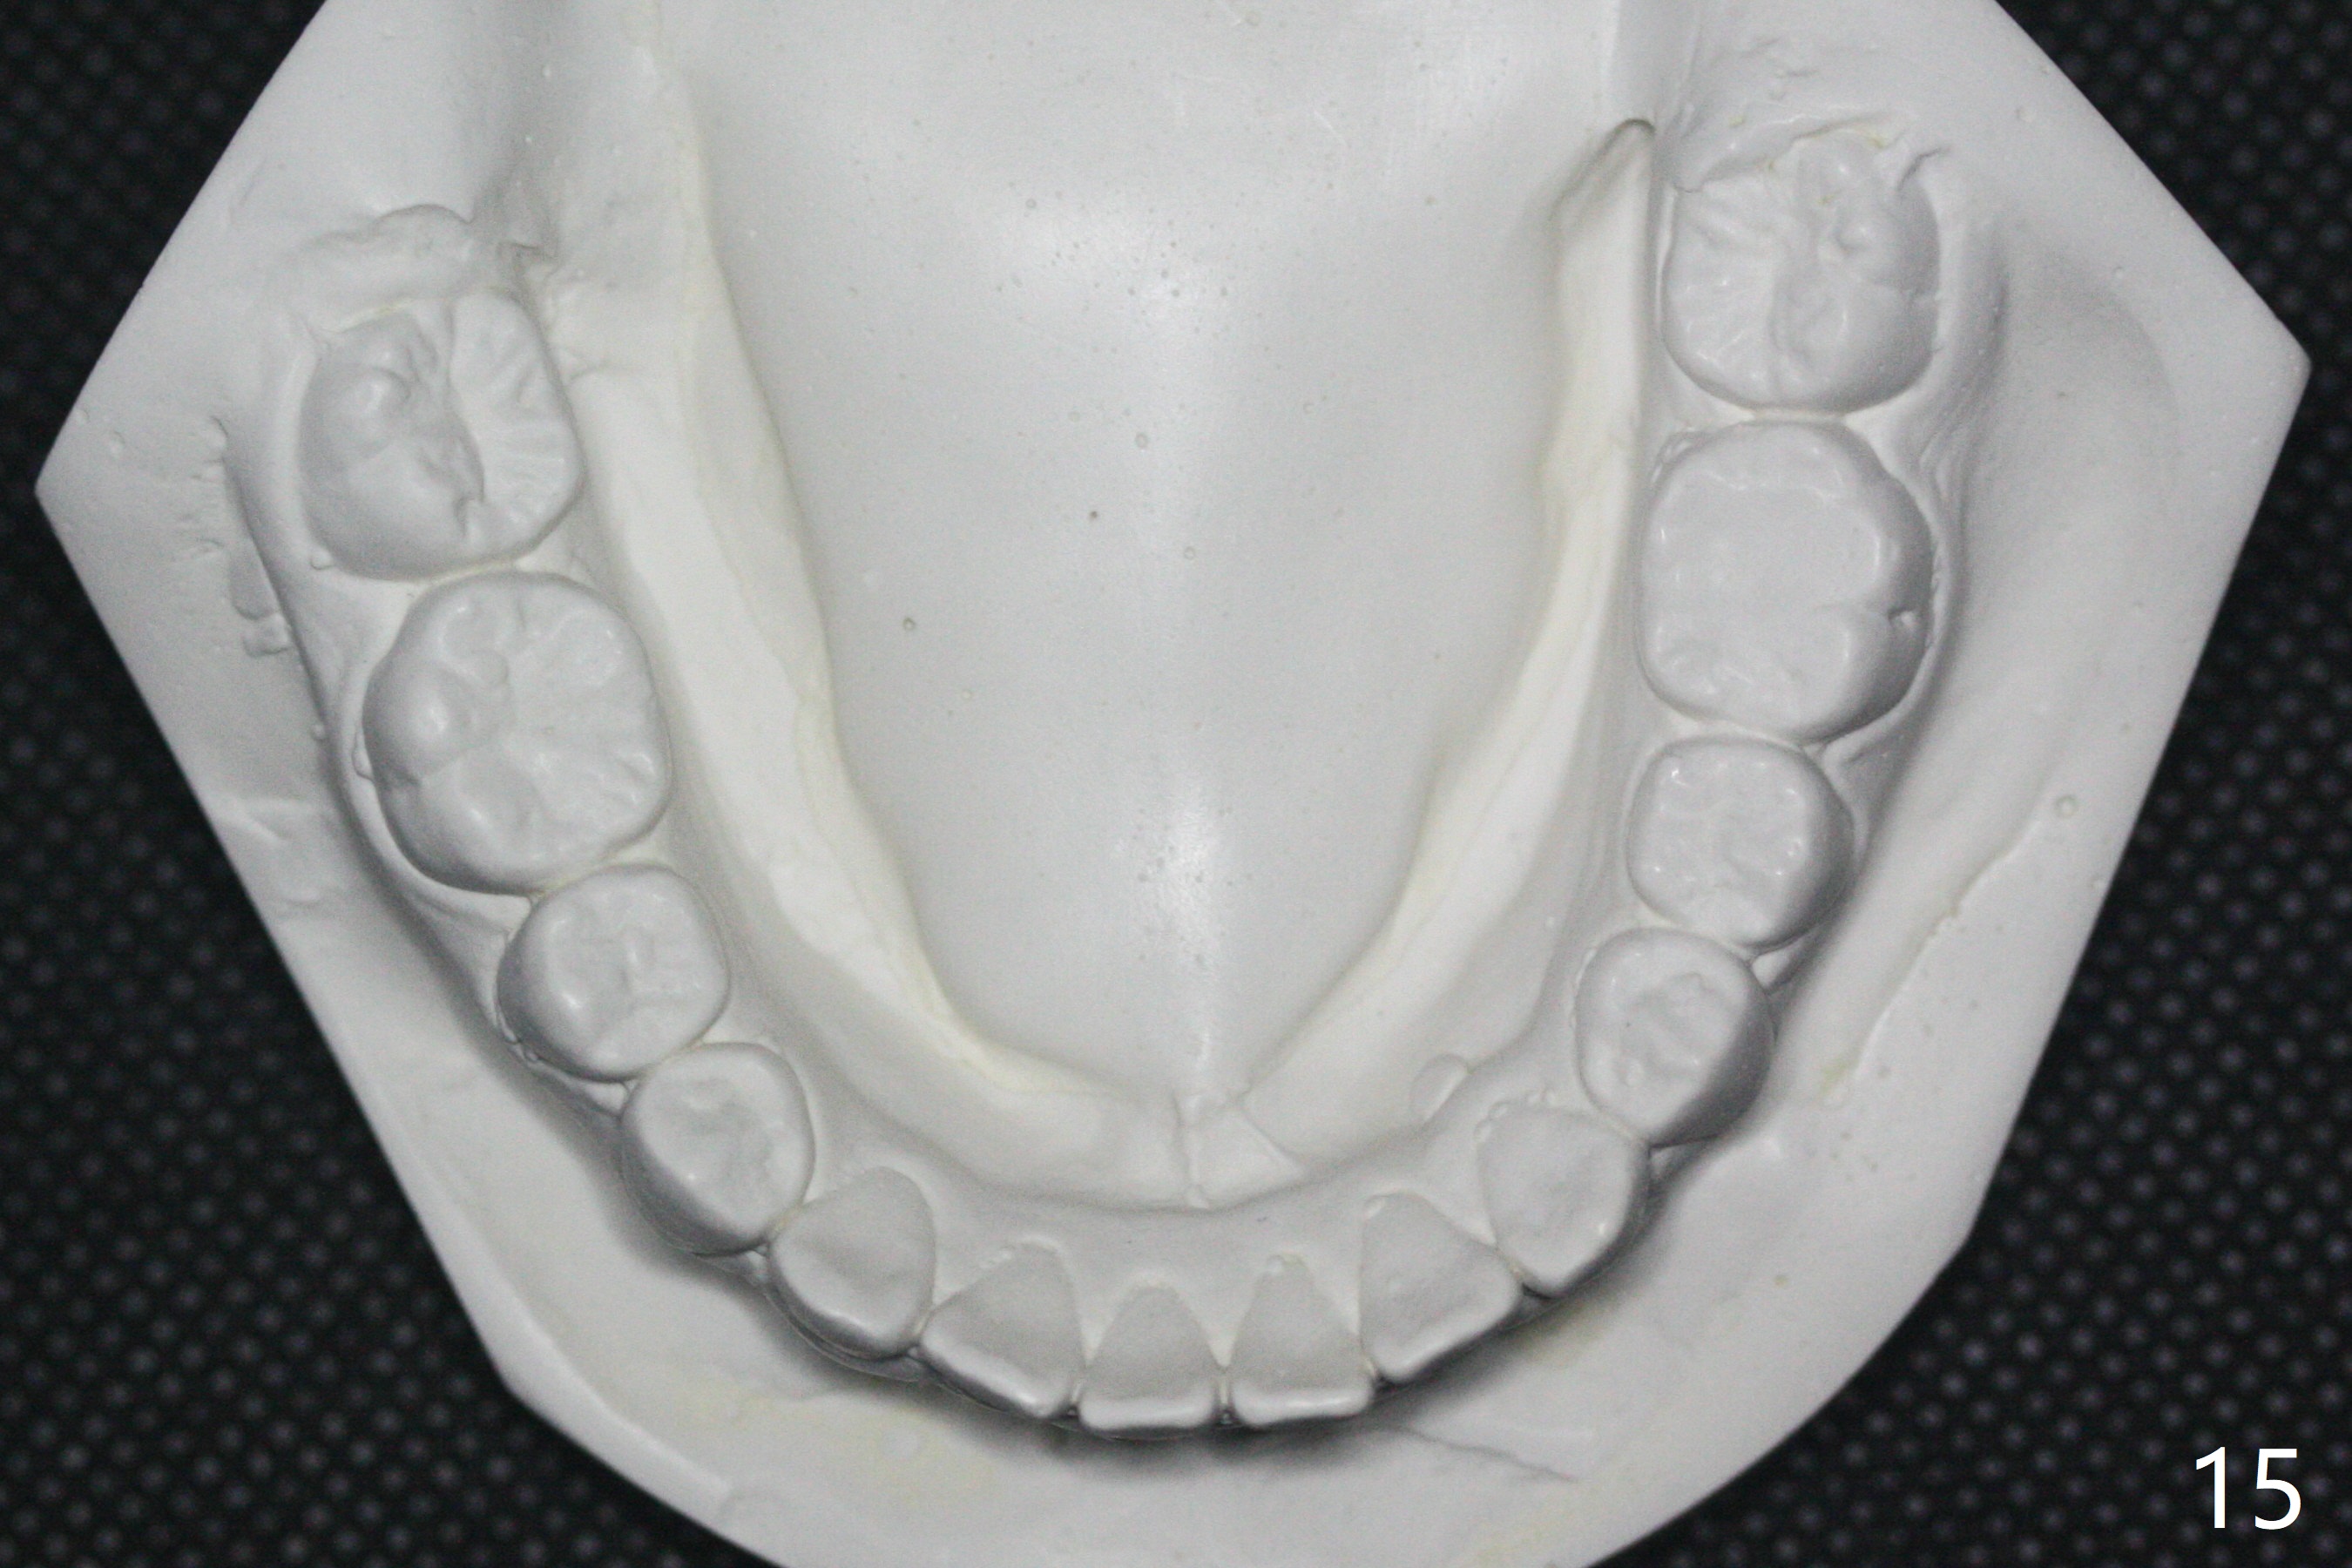

A 14-year-old woman, used to be a dental phobic (Fig.13), agrees with orthodontic treatment. Her mother is concerned about UL1 protrusion (Fig.8,11) and decalcification (Fig.8 *) and UR4 cross bite (Fig.7,10,14). There is mild lip constraint (Fig.1,3), as related to light dental protrusion (Fig.2,4), although the upper dental midline is not deviated (Fig.2). History shows that UR3 erupts before UR D is extracted, which is associated with UR4 cross bite. After arch expansion, consider proximal reduction to reduce anterior overjet if present. In fact that latter is not done; instead Class II is conducted.